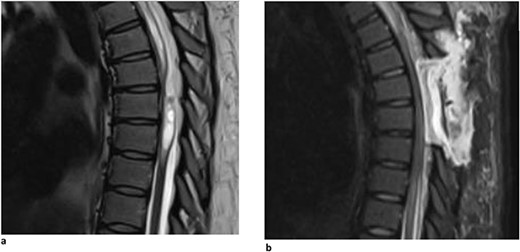

A 67-year-old man presented with a 1-year history of midline back pain that radiated down his right side and myelopathic symptoms. He stated that his symptoms worsened over the last year, and he felt generally weak in the lower extremities, causing problems with ambulation. He did not have any bowel or bladder incontinence, and there was no history of spinal surgery or syrinx expansion. MR imaging demonstrated a spinal cord indentation along the dorsal surface of the spinal cord at the T5 vertebral body level (Fig. 1a). It was hypothesized that the appearance of the spinal cord indentation was secondary to an arachnoid web. The patient underwent T5-T6 laminectomies for intradural exploration for arachnoid web resection at the level of the spinal cord narrowing. The arachnoid web was inspected, and the area of tether was identified and removed using microsurgical tools and technique (Video S1). Postoperatively, the patient reported improvement in back pain, increased strength within the lower extremities, and mild chest wall numbness. Follow-up MR imaging demonstrated resolution of the dorsal indentation and cord expansion (Fig. 1b).

(a) Dorsal indentation (scalpel sign) demonstrated in thoracic spine preoperatively (Patient A). (b) Postlaminectomy and resection of posterior arachnoid web demonstrating resolution of dorsal indentation and cord signal changes (Patient A).

A 40-year-old woman presented with a 3-year history of progressively worsening interscapular pain radiating around the rib cage on the right, difficulty with ambulation, and right foot numbness. Physical examination demonstrated myelopathic symptoms, with 3+ reflexes in both lower extremities, clonus, and Babinski, as well as difficult tandem gait. Thoracic MRI showed an arachnoid web at the T5-T6 vertebral levels (Fig. 2a). The patient underwent a T5-T6 laminectomy with intradural exploration. A large arachnoid web was encountered and resected using microsurgical tools and technique. Postoperatively, the patient reported improvement in her pain and ambulation. Follow-up MR imaging demonstrated resolution of the dorsal indentation and cord expansion (Fig. 2b).

(a) Dorsal indentation demonstrated in thoracic spine preoperatively (Patient B). (b) Postlaminectomy and resection of posterior arachnoid web demonstrating resolution of dorsal indentation and cord signal changes (Patient B).

A 62-year-old woman presented with an extensive, multi-decade history of lower back pain that has progressively gotten worse over the last year. She initially presented in clinic with lumbar pain that radiated down her left anterior thigh, as well as significant thoracic pain that worsened with activities. She has a past surgical history of three lumbar laminectomies in 1983, 1988, and 1995 that caused temporary relief of her lumbar radiculopathy. In clinic, she stated that, during long periods of standing, she will experience buttock and lower extremity pain, as well as pain radiating to her anterior thigh and groin. She also said that she had increased difficulty with balance, causing her to use a rolling walker for ambulation. Physical examination demonstrated myelopathic symptoms with 3+ reflexes in both lower extremities and positive Babinski sign bilaterally. MR imaging of the spine was ordered and showed an arachnoid web displacing the spinal cord at the level of T3 (Fig. 3). Her current symptoms were treated nonoperatively with an epidural steroid injection that caused 80% relief of symptoms for 2–3 weeks. Three months later, she returned with increased bilateral shooting pain in the interscapular blade region. The patient will return in 6 months to proceed with a repeat thoracic MRI to evaluate for any interval changes.

Dorsal indentation demonstrated in thoracic spine preoperatively (Patient C).